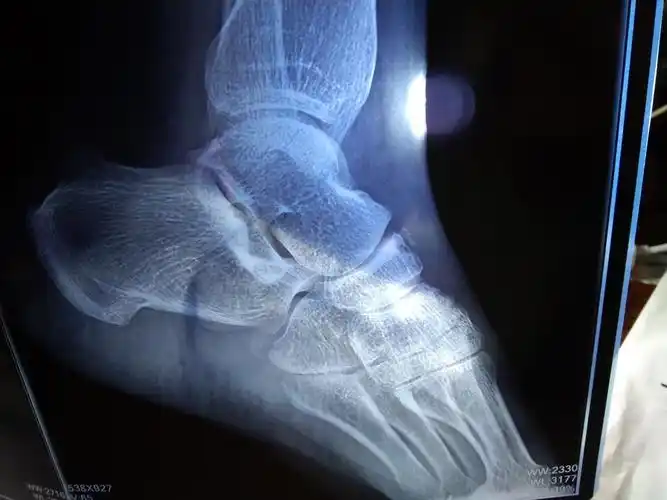

60天不放心还去拍了片子,骨折线已经模糊,但是错位的地方还是没有连接

门诊拍了个片子,没事.没有骨折,没有脱位

2开车被撞到,导致脚崴了,求各位大神看这样的片子有没有问题,到现在半

10月15日手术.已经术后20天 请问什么时候可以走路,片子是术后3天

看个足部的片子